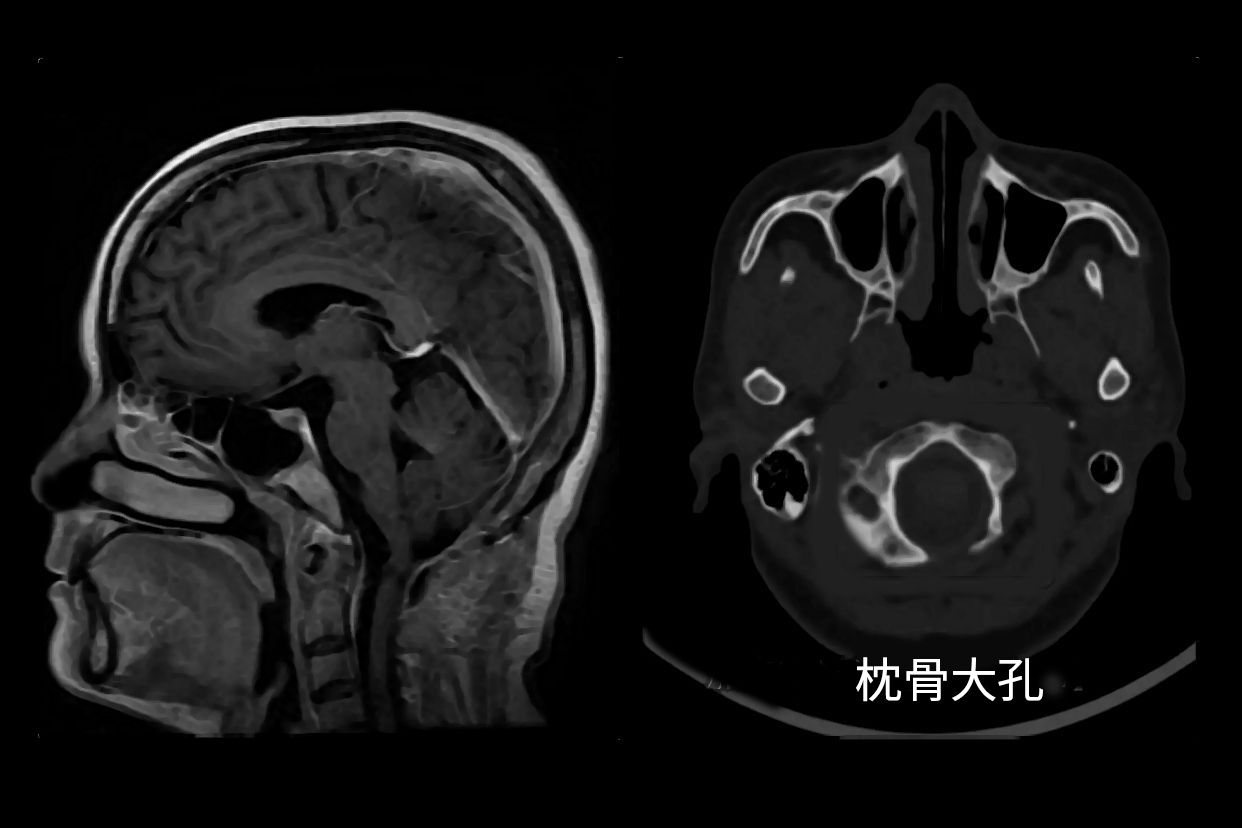

枕骨大孔ct解剖图

(a图)小脑扁桃体延伸至枕骨大孔的下方(白色弯曲箭头),脑干挤压斜坡

当小脑扁桃体向下疝出超过枕骨大孔下缘5mm即可诊断为小脑扁桃体下疝